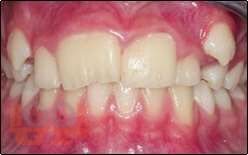

В пособии представлены вопросы этиологии, клиники, диагностики, лечения зубочелюстных аномалий и методы их комплексной профилактики.

Включает в себя тему изменений в околозубных тканях в процессе ортодонтического лечения, описаны ортодонтичекие силы, различные теории перестройки костной ткани, изменения в ВНЧС при перемещениях нижней челюсти. Описаны причины рецидивов как таковых, так и отдельных нозологических форм зубочелюстных аномалий, а так же рекомендации для надежного ретенционного периода и уменьшению рисков возникновения рецидива. Учебное пособие предназначено для студентов, обучающихся по специальности 31.05.03 «Стоматология».